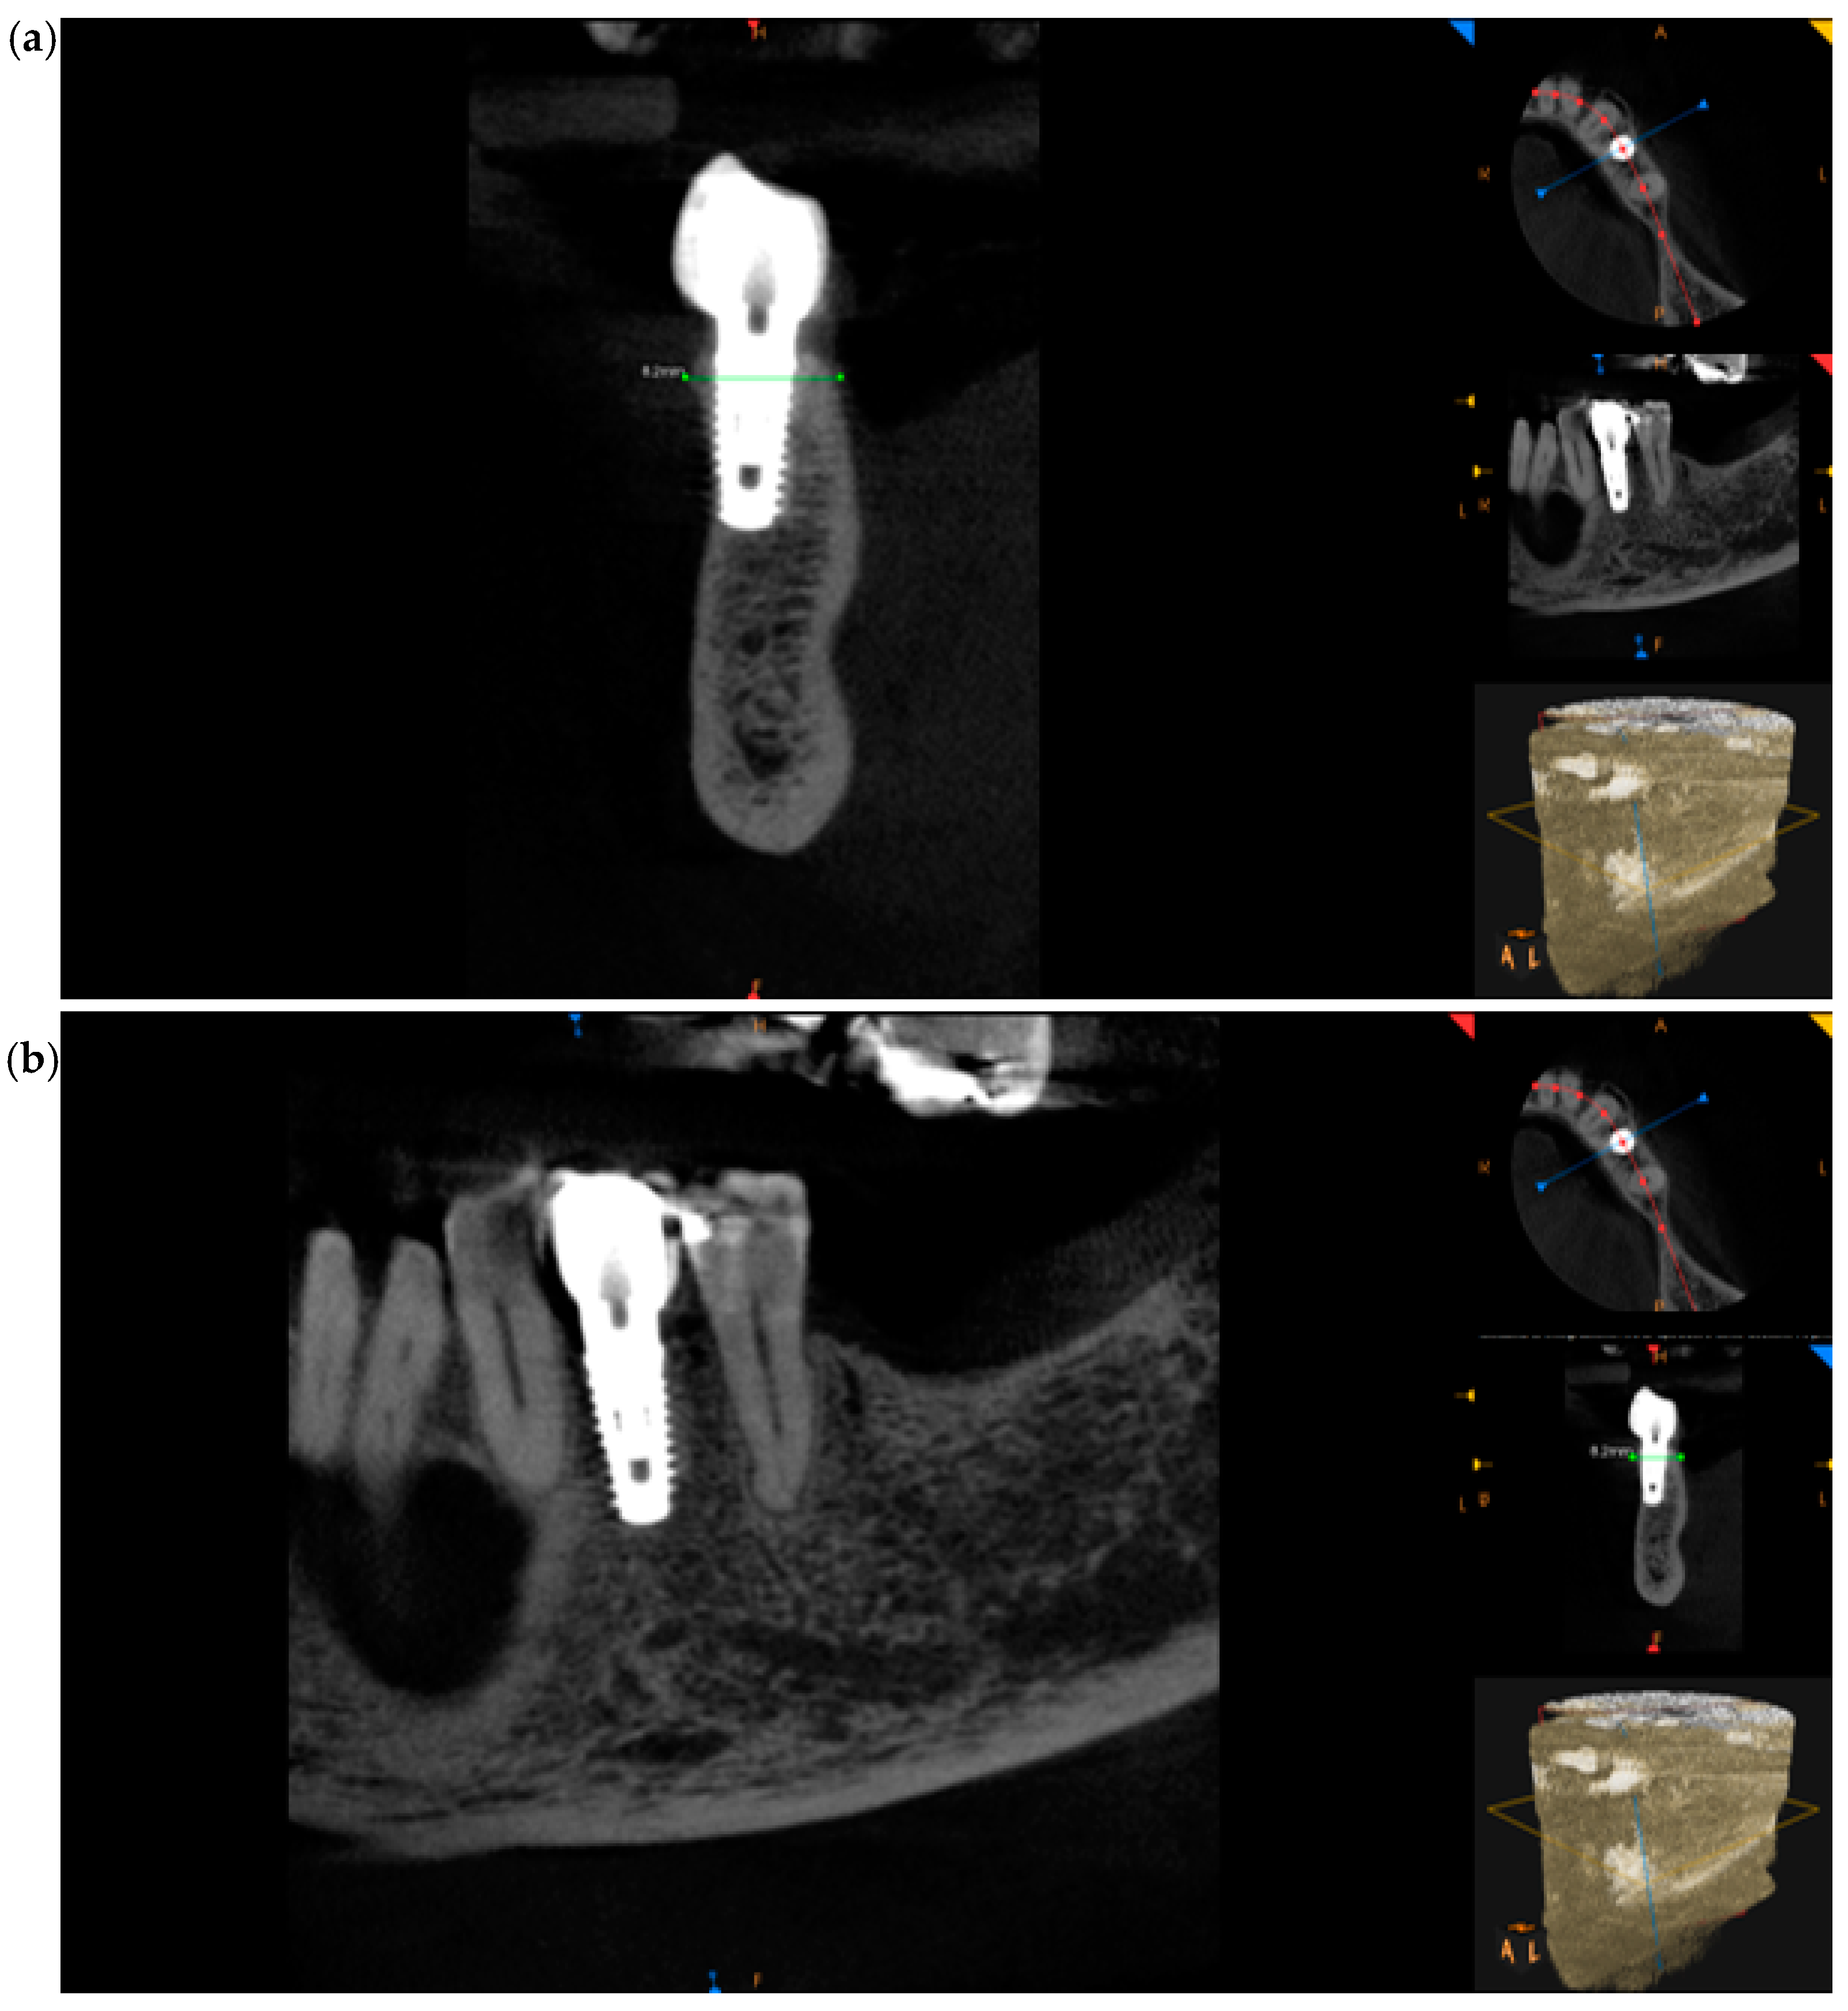

At 4 months, CBCT was performed to check the hard tissues, which confirmed a correct healing pathway with maintenance of the initial dimensions (Figure 4a–c).

Taking the remaining teeth as a reference, we positioned ourselves in the same coronal cuts, measuring the bone thickness. At the site of interest, the preoperative CBCT showed a ridge width of 8.30 mm that was maintained (Figure 9a,b). Following a 4-month period, the CBCT follow-up revealed that the alveolar ridge dimensions had been successfully preserved, with the ridge width remaining at 8.30 mm. This result implies that the bone resorption at the fenestration site was successfully inhibited by the Periosteal Inhibition (PI) approach.

Figure 4. CBCT images at 4 months after the surgery: (a) frontal section, (b) transversal section, and (c) sagittal section.